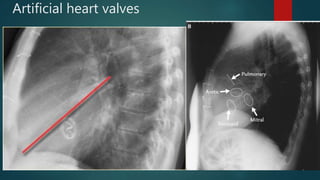

Artificial heart valves

 localized by drawing a

longitudinal line through

the mid sternal body. Use

this line to bisect the

sternum in the sagittal

plane and then draw a

perpendicular line dividing

the heart horizontally.

 localized bydrawing a longitudinal line through the mid sternal body. Use this line to bisect the sternum in the sagittal plane and then draw a perpendicular line dividing the heart horizontally.

• #24 The location of the cardiac valves is best determined on the lateral radiograph. A line is drawn on the lateral radiograph from the carina to the cardiac apex. The pulmonic and aortic valves generally sit above this line and the tricuspid and mitral valves sit below this line